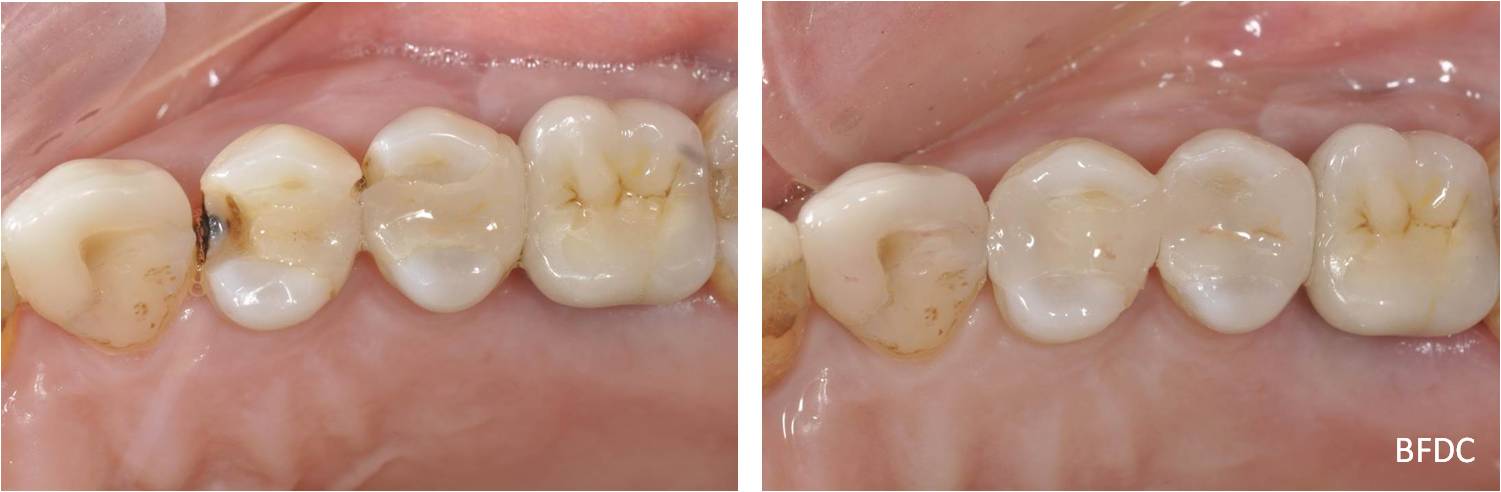

陶瓷崁體-二次蛀牙-#24、25

術前、術後比較